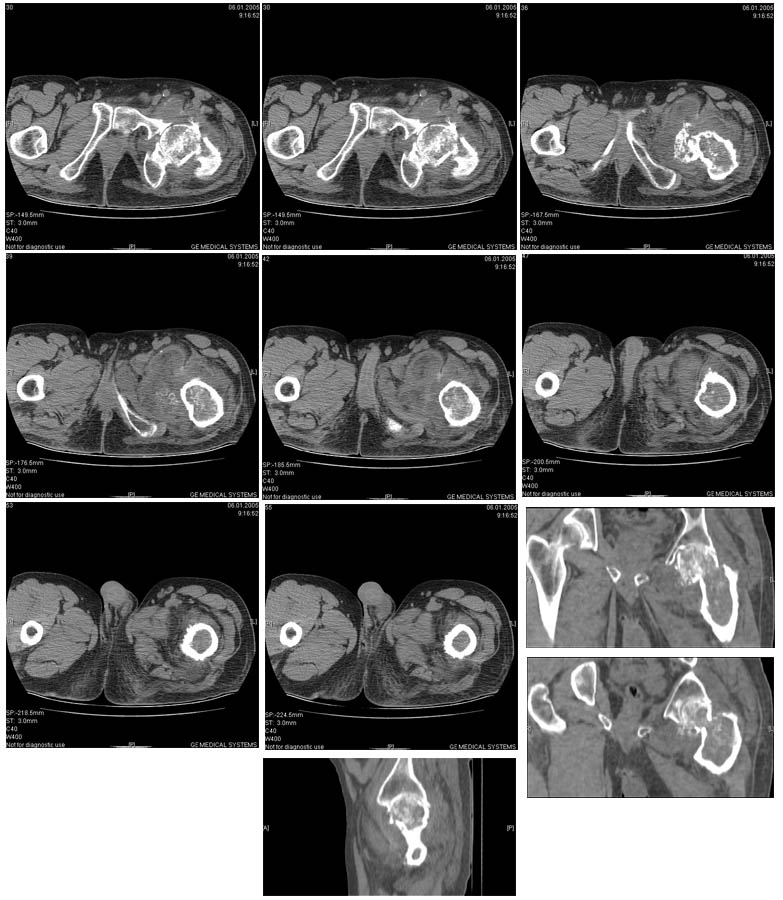

И снова вопрос по эндопротезированию: Пациенту 51 год. Болен с 2000 г, когда отметил умеренные, нараостающие боли в в/3 левого бедра, прогрессирующую контрактуру лев Т/Б сустава.

05.12.04 после падения на бедро боли резко усилились, нога стала неопорной. На рентгенограмме обнаружен патологический перелом шейки бедренной кости. Обследован в отделении костной онкологии. Результат биопсии: асептический некроз проксимального отдела бедренной кости. Вопрос: выбор технологии эндопротезирования - цементная или бесцементная версия. Заранее благодарю! С уважением,А.В.Владзимирский

Проксимальный отдел бедра не виден достаточно на представленных рентгенограммах; но то, что видно, как раз наводит на мысли о цементной фиксации - цилиндрический канал, измененный calcar, кистозные изменения в области большого вертела и т.д.

Evgueny Tchekashkine 01 Февраль 2005, 04:15

Как то очень подозрительно выглядит проксимальный отдел бедра для такого очень простого гистологического заключения. Вы уверены, что гистология настолько благополучна и в каком варианте она выполнялась: пункционная или открытая с забором костного блока? Не уверен на все сто , но область проксимального отдела бедра - одно из излюбленных мест для гигантоклеточной опухоли, которая зачастую озлакочествляется (имел два подобных наблюдения). Из своей практики могу сказать, что, к сожалению, информативность пункционной биопсии не сравнима с открытой техникой. Поэтому прежде чем решать цементный или бесцементный протез использовать, я бы повторил биопсию в сочетании со сканированием скелета, сывороточная щелочная фосфатаза, кальций, фосфор сыворотки, СОЭ, С- реактивный белок,

Вполне вероятно, что разговор может пойти об опухолевом протезе или Вагнере...

Soglasen s Евгений И Чекашкин, proximal Femur does not look right. Sarcoma? Pagets, Osteomyelitis?. Technicality of the implantaion will be dependent upon underlying pathology, and the surgeon's level of comfort.

Действительно, проксимальный отдел бедра выглядит подозрительно. По-моему напоминает болезнь Педжета. Кстати, гистологическое заключение в таком случае часто звучит как "хроническое воспаление", "асептический некроз с элементами лейкоцитарной инфильтрации" и т.п. Далеко не все патоморфологи имеют достаточный опыт для дифференцировки костной патологии.

Однако, вне зависимости от диагноза, проблема "с цементом или без" остается. Онко-эндопротезы (так же как и ревизионные) тоже могут быть бесцементной фиксации. И в нешей клинике есть положительный опыт их применения. Поразительно, насколько полярными могут быть мнения в этом вопросе, причем аргументация ссылками на литературу практически лишена смысла - достаточно много статей с равной степенью уверенности пропогандирующих и то и другое. Ссылки на собственный опыт тоже имеются разные. Лично я больше склоняюсь к бесцементной технике. Однако советую запастись и цементными компонентами и окончательно решить, что применять во время операции.